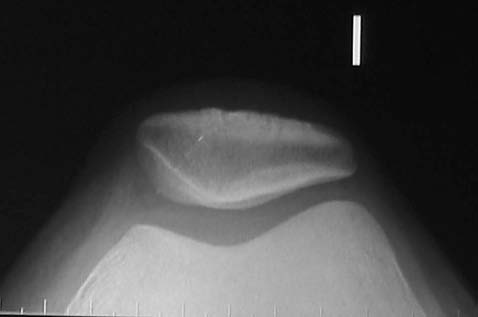

RX simple: buen eje patelofemoral, no se halló evidencia de cuerpo libre osteocondral. (Fig. 1)Resonancia magnética: se identificó una tumoración en el alerón patelar medial, circunscripta, de 7mm de diámetro, localizada en el sector parapatelar medial, a nivel del plano de sección transversal mediopatelar.T1-T2 sin y con gadolinio. (Fig. 2 A-B)

Figura 1: Rx Merchant. Buen eje patelo femoral